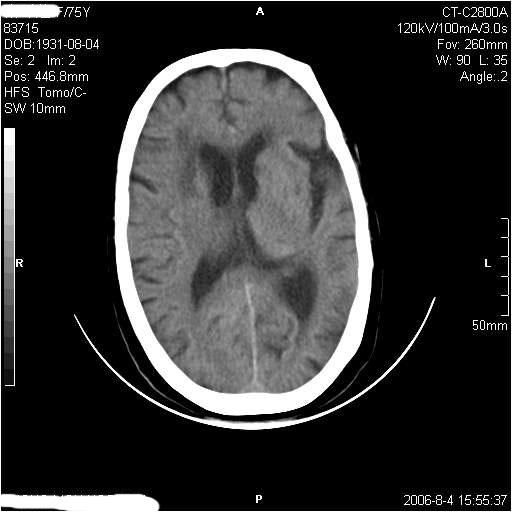

左侧偏瘫3天.

有摔倒外伤史,另看右侧灰白质界限.

双侧基底节区多发性腔梗.引起临床症状的主要原因是右侧侧脑室旁的梗塞病灶.

1、该患者从脑实质表现情况看应该年龄较大了,双侧基底节区多发斑片状低密度灶,侧脑室旁白质密度减低,各脑室腔扩大,脑沟裂增宽加深,以上改变符合:皮层下动脉硬化性脑病。

2、上纵裂右侧梭形条状高密度影阴,边缘模糊,周围水肿带环绕,右侧脑室受压变形,有摔倒外伤史,多考虑:纵裂硬膜下血肿。